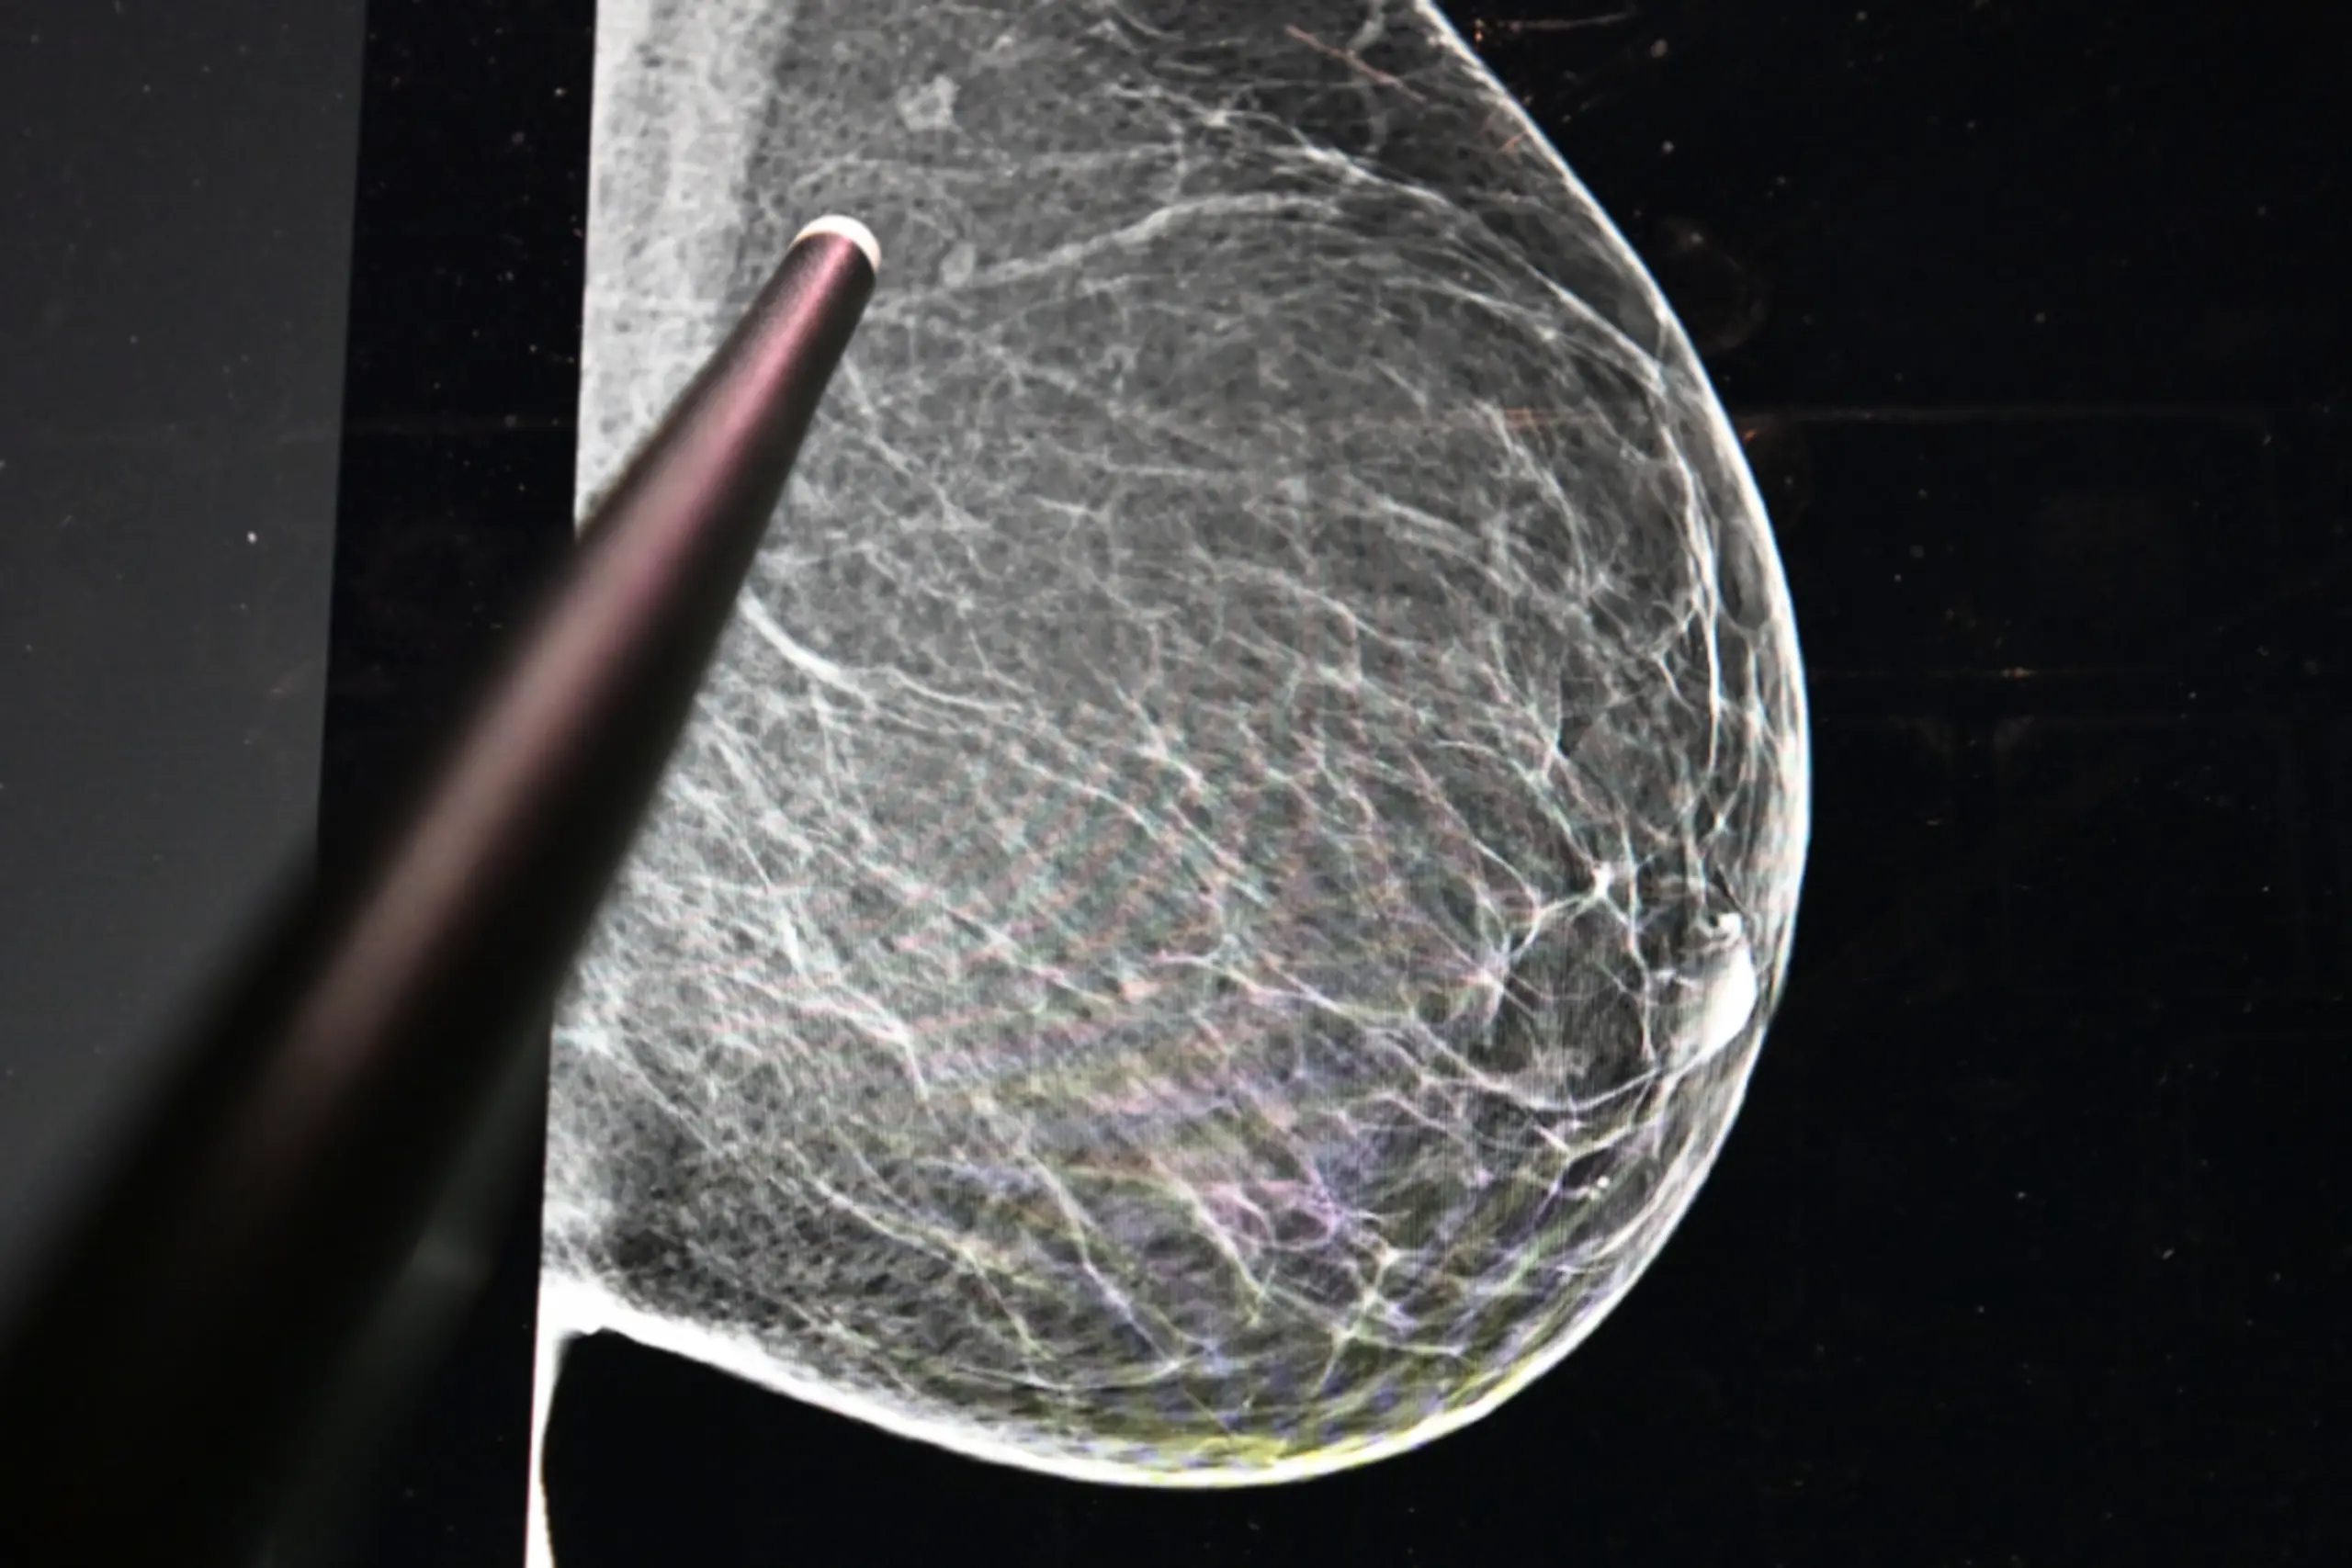

Auch bei der finanziellen Soforthilfe zeige sich dieses Bild: Von 530 dokumentierten Fällen entfielen 424 auf weibliche und 106 auf männliche Patienten. Besonders hoch ist der Bedarf bei Brustkrebspatientinnen. Hier verzeichnete die Krebshilfe 2025 rund 8.000 notwendige Beratungen sowie etwa 250 Fälle finanzieller Soforthilfe, hieß es in einer Aussendung am Donnerstag.